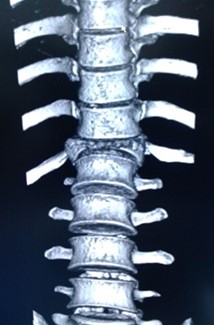

Volver a los detalles del artículo Espondilodiscitis tuberculosa. Presentación de un caso